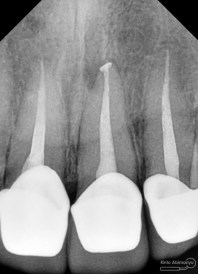

dan ini foto ronsen nya…

Dari pemeriksaan radiografis lokasi fraktur menyerempet kamar pulpa pada ketiga gigi tersebut… Saya sampaikan kepada pasien bahwa ketiga gigi tersebut memerlukan perawatan saluran akar terlebih dahulu baru kemudian dilanjutkan dengan restorasi indirek… kenapa saya pilih restorasi indirek? Pertimbangannya adalah sisa struktur mahkota gigi yang ada bila hanya di “sambung” dengan restorasi direk dalam jangka panjang rentan mengalami kerusakan, yang kedua pemilihan warna akan lebih maksimal pada kasus ini…. Pasien setuju dengan rencan perawatan yang saya jelaskan…